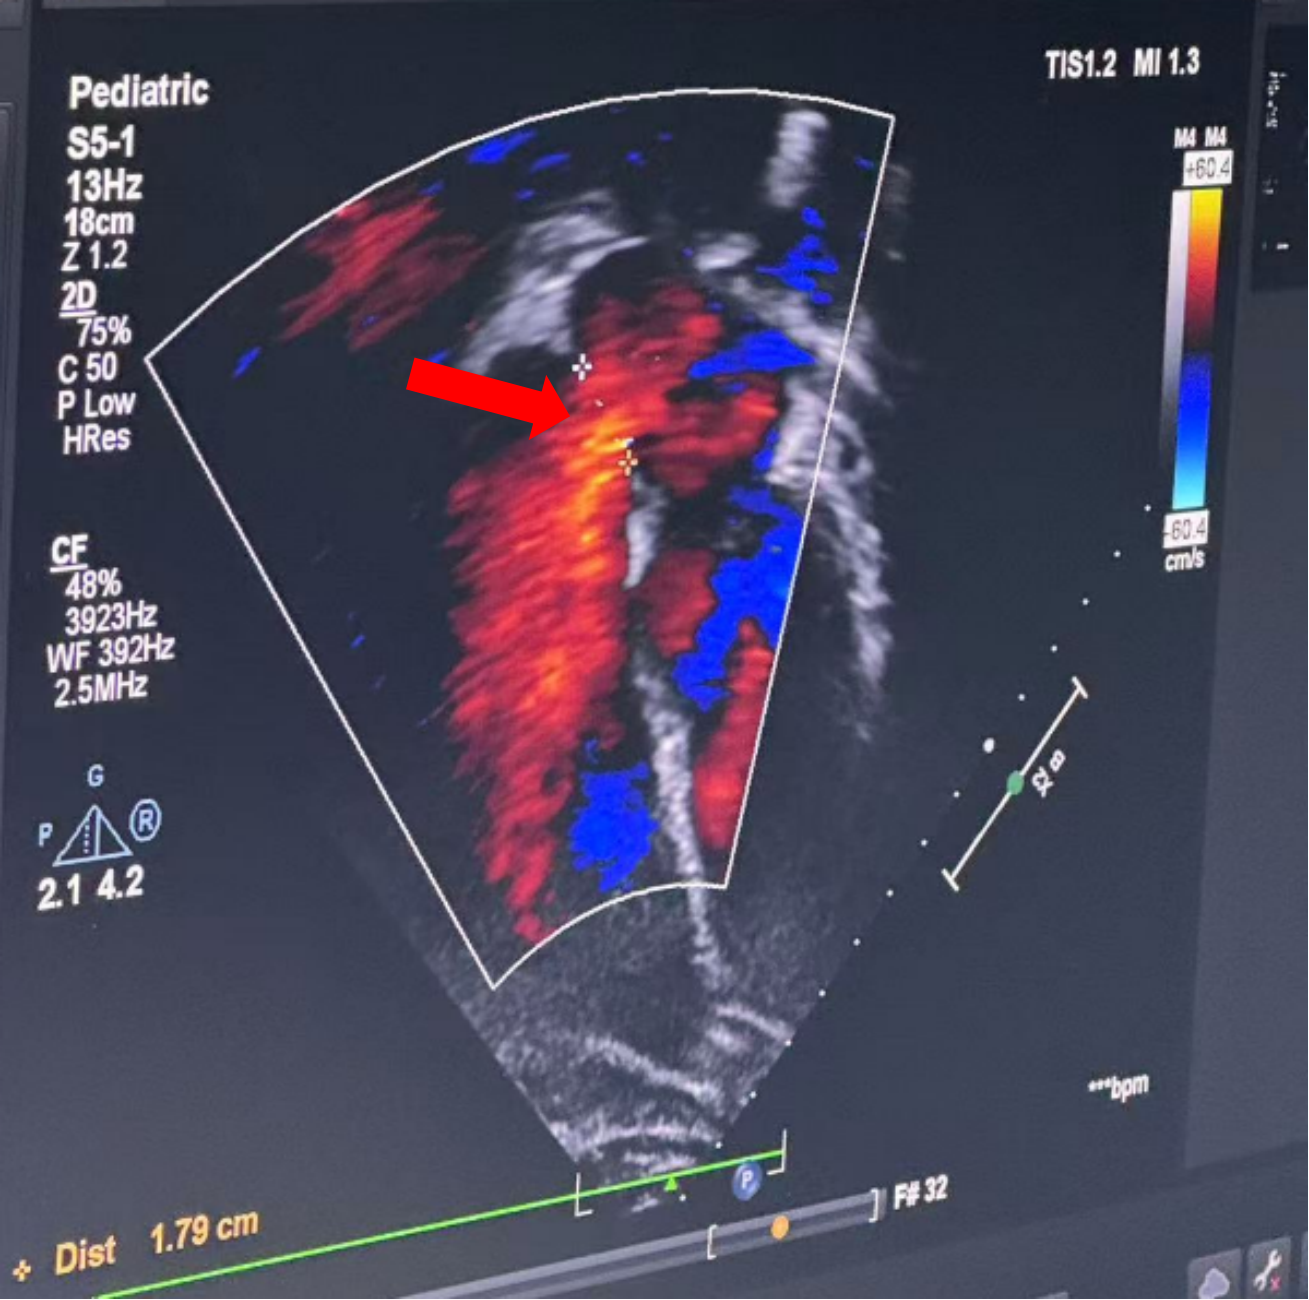

二维超声心动图:患儿年长,体脂厚,切面探查显示不清。心脏位置及连接正常。右房右室增大、主动脉无增宽,肺动脉增宽。房缺缺损约17.7mm(继发孔型),二维显示房间隔缺损约15.9mm,彩色束宽约17.3mm(软边约10.8mm,非飘软)。胸骨旁四腔:距二尖瓣缘26.0mm,距房顶缘约7.2mm;剑下两房心:房隔总长约45.6mm,距上腔缘约14.6mm,下腔缘约19.9mm。室间隔完整,房室瓣开放活动正常,左位主动脉弓。左冠状动脉开口位置正常,右冠状动脉开口显示不清。

多普勒超声心动图:各瓣膜血流速度正常。ASD L→R(+);MR(-);TR(+),轻度2.8m/s;Al(-);PI(+),轻微。

术中复测及封堵策略:术中超声复测缺损大小约19.1×17.9mm,经综合评估后,决定经股路径介入,选择BDASD-I 28可降解封堵器、16F可降解封堵器介入输送系统进行封堵,手术全程通过超声+DSA引导进行。